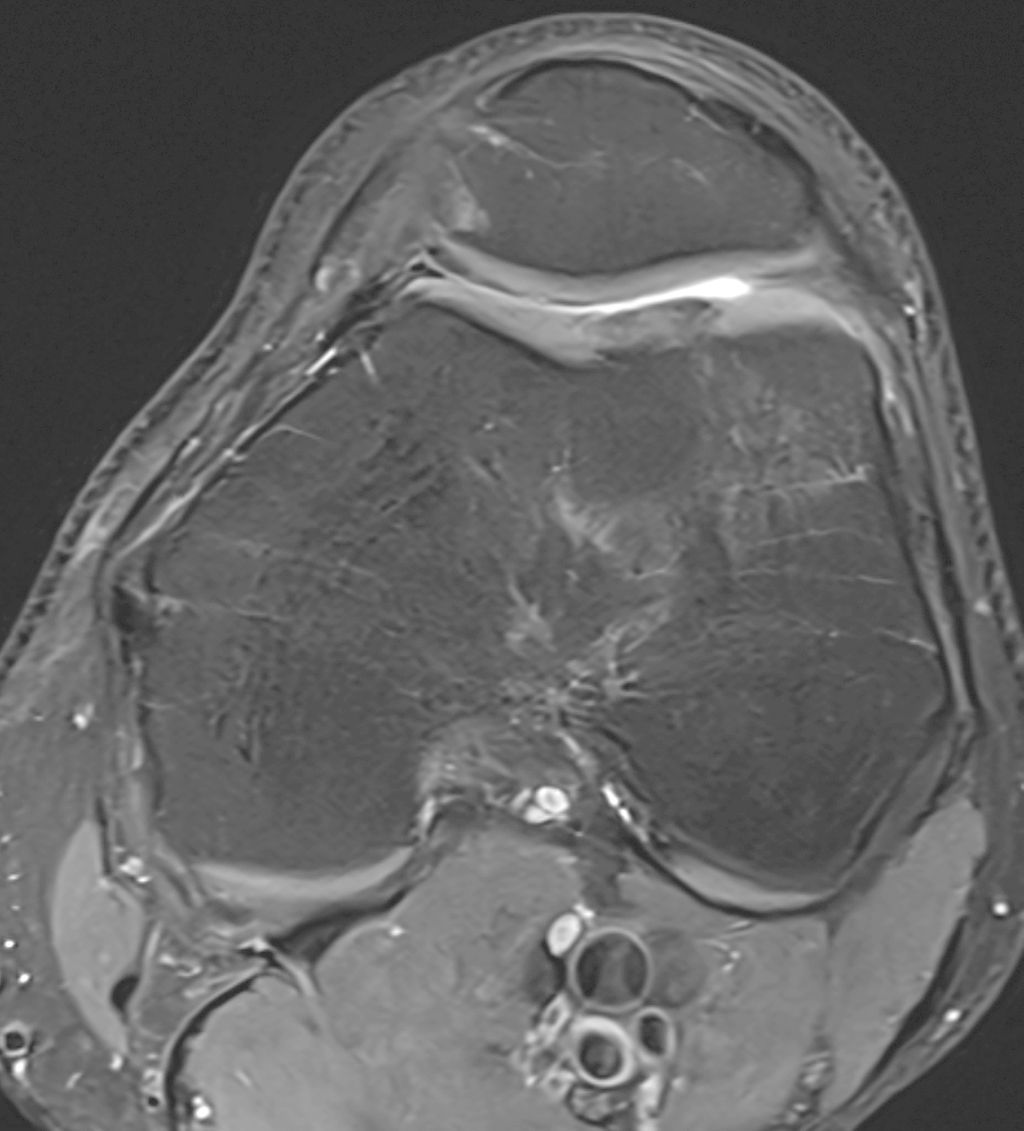

Abb. 1a und b: MRI-Bildgebung präoperativ bei grossem, vollflächigem Knorpelschaden an der medialen Femurkondyle einer jungen Patientin